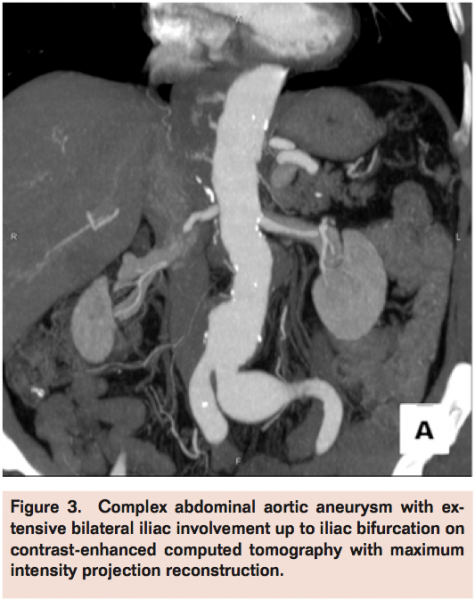

The decrease in open surgery volume for AAA repair in the last decades after the introduction of EVAR is mainly justified by well-demonstrated, consistently lower perioperative risks with new mini-invasive techniques despite the more uncertain durability often requiring reinterventions.9,10 Development of more advanced technologies and devices (fenestrated, branched stent-graft, etc.) progressively expanded the range of suitability for endovascular approaches also in the presence of more challenging and adverse AAA anatomies, such as large and angulated necks, small iliac arteries, and extensive aneurysms. Nevertheless, morphology is still the main and probably irreversible reason of concern for EVAR. Forced application of EVAR when not suited for AAA morphology (Figures 1-4) produces increased failure and complication rates. Schanzer et al reviewed outcomes of 10,228 EVAR performed in a 5-year period in the U.S. and found that only 42% of patients had an anatomy that met the most conservative definition of device instructions for use. The 5-year post-EVAR rate of AAA sac enlargement was exceptionally high at 41%. Notably, the rate of AAA sac enlargement was significantly higher in patients who underwent EVAR outside the instructions for use.11 Therefore, despite the feasibility in deployment, long-term efficacy of EVAR in forced AAA anatomies remains a main drawback allowing these cases to be better pursued by an open surgical approach.

Costin et al published their open AAA practice following the institution of an EVAR program in 2006.5 Authors compared 301 patients (group 1), who underwent open repair before, with 305 patients (group 2) who underwent open repair after the beginning of the stent-graft program experience. They found a significant increase in number of repairs requiring suprarenal clamping, from 6% in the pre-EVAR period to 20% in the initial post-EVAR period. Furthermore, there was higher iliac complexity in the second period: iliac aneurysms were present in 25% of group 1 patients and 42% of group 2 patients (P<.05). The incidence of associated iliac occlusive disease was 12% in group 1 and 20% in group 2 (P<.05).

More recently, Hiromatsu et al compared their perioperative data with open AAA surgery before (n=99) and after (n=125) the EVAR era.13 In the post-EVAR period, the authors found greater need for suprarenal clamping (11.2% vs 3%), a higher proportion of octogenarians (23.2% vs 11.1%), and extensive iliac involvement (35.2% vs 22.2%).13

Thereby, open aneurysm repairs are currently performed primarily in patients with more extensive aneurysms or who are not anatomically suitable for EVAR with the main limitation being an anatomically unfit proximal neck (short, large, thrombosed, angulated) or in patients with EVAR failure (eg, conversion after stent-graft migration, persisting endoleak with aneurysm growth, stent-graft rupture, etc.). Severe vessel calcification, iliac access obstruction, extensive iliac aneurysm extension, and previous aortic graft infection are other common findings in AAAs mainly reserved today for open surgery. These anatomical changes may also pose higher technical challenges for open surgery, such as raised frequency of suprarenal clamping or visceral revascularization and increases in operative duration, use of blood products, intensive care unit stay, hospital length stay, and overall complication rates when compared to repairs in more straightforward and infrarenal AAA, now routinely treated by EVAR.